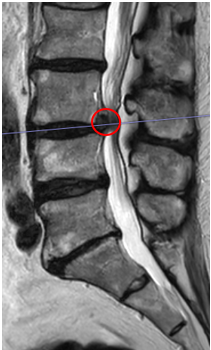

治療前

腰椎MRIで画像検査をしたところ、赤い枠で囲った箇所(L3/4)に椎間板ヘルニアができていました。